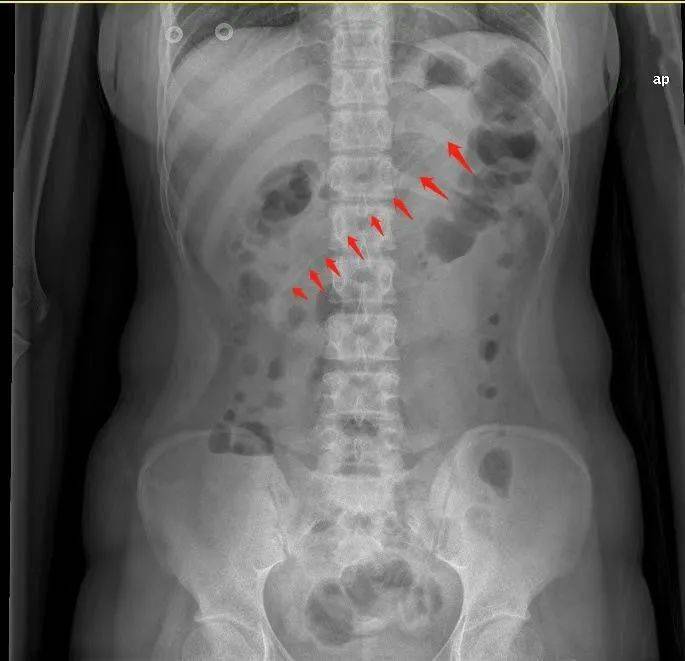

腹部X线检查显示 , 小李胃中的 勺子长达17厘米 , 因此胃镜下取异物有较大的难度 。 但如果不取出 , 患者可能会出现消化道梗阻、出血和穿孔等并发症 。 因此 , 胃镜下取出异物势在必行 。

历经40分钟 , 一根长约17cm的粉色塑料勺子终于从胃内取出了 。

术后取出的约17厘米长的勺子